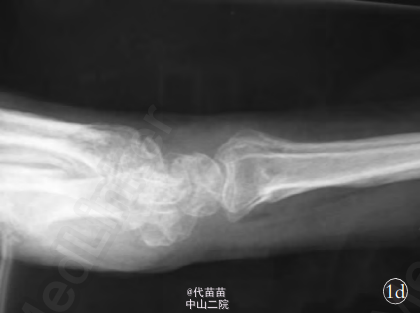

患者,女,54 岁,3 个月前不慎摔倒,右腕部着地,当即出现右腕肿胀、畸形、功能受限,于当地医院拍片后诊断为“右桡骨远端骨折、右尺骨茎突骨折”,予以骨折手法整复术,石膏托外固定。 2 个月后去除石膏托行功能锻炼,发现右手尺侧麻木不适,右手无力伴肌萎缩,小鱼际萎缩明显,抓握无力,且症状渐进性加重。在当地医院予以神经营养药物内服治疗,效果不佳,遂来本院诊治。门诊以“右尺神经损伤、右桡骨远端陈旧骨折、右尺骨茎突陈旧骨折”收入院。 入院查体:右手部肌肉萎缩,以骨间肌、小鱼际肌明显;右中环小指呈屈曲畸形,不能伸直,右手并指分指困(见图 1a,1b);右腕尺侧压 痛 明 显 ,前臂旋转功能受限。右小指掌侧及环指尺侧刺痛觉减退,夹指试验阳性。X 线片示右桡骨远端陈旧骨折、右尺骨茎突陈旧骨折(见图 1c,1d)。 肌电图(electromyography,EMG)检查见:右上肢尺神经远端支配肌见自发电活动, 见小指展肌少量新生电位。神经传导速度(never conduction velocity,NCV)检测示右上肢尺神经远端感觉运动传导未引出。 神经干动作电位(nerveaction potential,NAP)检测示神经干电位传导双侧对称。 提示:右上肢尺神经腕部不完全损伤电生理表现。诊断:右尺神经损伤;右桡骨远端陈旧骨折;右尺骨茎突陈旧骨折。 在臂丛麻醉下行右尺神经损伤探查松解术。 术中于右腕掌尺侧缘尺神经走行部位 ,取“S”形切 口 长 约 10 cm,逐 层 暴露,见尺神经在腕部走行异常,同时取腕背尺侧纵行切口长约6 cm,在显微镜下沿尺神经仔细分离,发现尺神经绕尺骨小头颈部近端尺 侧 至 尺 骨 小 头 背 侧 卡 压 于 尺 骨 茎 突 骨 折 端 部 位(见图 1e),神经明显充血、变细、变长,与周围组织粘连严重。摘除尺骨茎突碎骨快,予以尺神经彻底松解(见图 1f)。 术中见三角纤维软骨损伤,予以修补,神经外膜下注射得宝松,并用可吸收生物膜包裹,防止术后神经粘连。 术后 1 d 患者自觉疼痛缓解,环、小指麻木减轻,3 周后拆石膏托开始功能锻炼。5 个月后随访,患者自觉症状全部消失 ,环、小指感觉恢复正常,手指伸直、屈曲功能及分指、并指功能良好(见 图 1g,1h,1i),小鱼际肌及骨间肌萎缩明显恢复,前臂旋转功能良好。 本例患者受伤时,腕关节处于背伸位,前臂旋前,手掌着地,强大的暴力作用于手掌,桡骨远端骨折向背侧移位,腕缺乏支撑,造成腕尺侧继续损伤,尺骨茎突骨折及腕部三角纤维软骨损伤, 同时桡骨骨折近端及尺骨茎突骨折近端向掌侧重叠移位, 使尺骨茎突骨折端嵌插于尺神经的掌尺侧,导致尺神经绞索于尺骨小头桡背侧及尺骨茎突骨折近端,此时经手法牵引复位后,造成尺神经被卡压于骨折断端。其损伤机制不同于通常的桡骨远端骨折引起腕尺管周围软组织的粘连、瘢痕使尺神经及其分支造成压迫而产生的尺神经损伤。因患者术后腕部肿胀、疼痛,再加上石膏托固定,患肢不能活动,很难在早期发现,极易漏诊而得不到及时处理。 因此手法复位前后需注意患指的感觉、运动情况,判断手法复位前后有无正中神经损伤或尺神经损伤。若发现损伤,必须立即做相应处理。 治疗方法:尺神经是支配手内在肌的主要神经,损伤后会对手部功能产生重要影响,损伤后修复越早,效果越好。 当腕部尺神经损伤诊断一旦明确,手内在肌萎缩,肌电图有失神经电位者,必须尽早行神经探查松解术,以便解除神经的压迫,改善神经局部的血流障碍,降低神经内液压,维持神经内环境的稳定性,促进纤维再髓鞘,恢复其正常的传导功能。 术中在显微镜下细心的彻底松解卡压的神经,避免二次损伤。术中神经虽然明显水肿、充血、变细 、变长,但仍有部分神经纤维连续,术前肌电图显示尺神经腕部不完全损伤电生理表现,故仅仅给予神经松解,未予切断重新吻合。 如卡压非常严重,无明显神经束相连,切除神经瘤,行神经的直接吻合或桥接神经移植。神经受伤的程度、位置、手术的时间、是否采用显微外科技术修复等与预后有密切的关系。 在上肢神经修复或神经松解术后尺神经效果最差,重要原因为尺神经主要支配手内肌,即使神经吻合质量好, 再生过程顺利, 待其生长到运动终板时,手内肌群及运动终板已萎缩失用,疗效不佳。此例虽卡压于骨折端的骨痂内3月余,但由于尺神经未完全损伤且术中在显微镜下精细的操作,未造成二次损伤,且损伤部位在腕部近手内肌处,手术后效果仍令人满意。